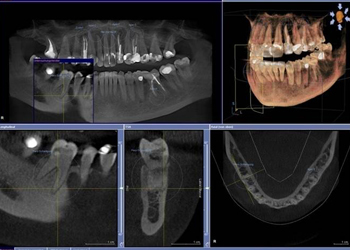

模型の作製や歯科用CTによる精密検査を行い、使用するインプラント体の種類や方法を決定。治療計画を立て、患者さんにお口の状態を丁寧にご説明し、ご質問などにはわかりやすくお答えします。患者さんにご納得いただけましたら治療の開始です。

| 治療内容 | 前歯インプラント治療/下前歯矯正治療 |

|---|---|

| 患者様の年齢 | 19歳 |

| 患者様の性別 | 女性 |

| 治療期間 | 1年 |

| 治療回数 | 矯正治療合わせて45回程度 |

| 治療費用 | インプラント治療50万円/矯正15万円 |